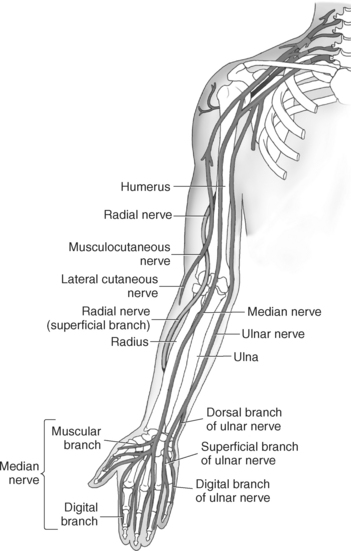

The brachial plexus, also described in Chapter 4, is a large network of nerves that innervate the upper limb (Figures 9.38 and 9.148). It extends from the neck into the axilla. The brachial plexus is formed by the union of the ventral rami of nerves C5-C8 and the greater part of the T1 ventral ramus. The ventral rami from C5 and C6 unite to form a superior trunk, the ventral ramus of C7 continues as the middle trunk, and the ventral rami of C8 and T1 unite to form an inferior trunk. Each of these trunks divides into an anterior and posterior division. The anterior divisions supply the anterior (flexor) parts of the upper limb, and the posterior divisions supply the posterior (extensor) parts of the upper limb. These divisions form three cords (posterior, lateral, and medial) that continue to divide to form the median, ulnar, musculocutaneous, and radial nerves (sequential Figures 9.59 through 9.67 and 9.87 through 9.95). These nerves supply the muscles of the forearm and hand. The median nerve descends the cubital fossa deep to the median cubital vein. It supplies the pronator teres muscle of the arm and all the superficial and deep flexor muscles of the forearm, except the flexor carpi ulnaris muscle. It gives off an anterior interosseous branch that descends within the forearm to supply the flexor digitorum profundus muscle. The median nerve courses through the carpal tunnel of the wrist, typically superficial to the flexor tendons (Figure 9.147). It supplies flexors of the hand, skin of the wrist, thenar eminence, palm of the hand, and sides of the first three digits and lateral half of the fourth. At the elbow, the ulnar nerve passes between the medial epicondyle of the humerus and the olecranon process within the cubital tunnel to enter the medial side of the flexor compartment of the forearm (Figure 9.148). Posterior to the medial epicondyle, the ulnar nerve is superficial and easily palpable. It supplies the flexor carpi ulnaris muscle and the medial side of the flexor digitorum profundus muscle in the forearm before entering the hand. The ulnar nerve passes under the flexor retinaculum, along with the ulnar artery, to enter the palmar compartment of the hand (Figure 9.147). At this point, the ulnar nerve divides into superficial and deep terminal branches that supply the ulnar flexors of the hand as well as the skin on the medial side of the palm, medial half of the dorsum of the hand, fifth digit, and medial half of the fourth digit. The musculocutaneous nerve descends to the lateral side of the arm and elbow to innervate the flexors in the arm and the skin of the forearm, wrist, and thenar region of the hand (Figure 9.146). It emits branches that supply both heads of the biceps brachii muscle, the brachialis muscle, and the elbow joint. It innervates the skin of the dorsal surface of the arm. A continuation of the musculocutaneous nerve is the lateral cutaneous nerve, which terminates into cutaneous branches that supply the skin covering the radial side of the wrist and the thenar eminence. The radial nerve is the largest branch of the brachial plexus. It passes inferolaterally around the body of the humerus in the radial groove (Figure 9.146). It continues inferiorly between the brachialis and brachioradialis muscles to the level of the lateral epicondyle of the humerus, where it divides into deep and superficial branches. The deep branches supply all the extensors in the arm and forearm, and the cutaneous branches innervate the skin on the dorsal side of the arm and hand. The superficial branch, the direct continuation of the radial nerve, is entirely sensory. It supplies skin and fascia over the lateral two thirds of the dorsum of the hand, the dorsum of the thumb, and proximal parts of the lateral three and one half digits on their dorsal surfaces (Figures 9.57 through 9.67, 9.87 through 9.98, and 9.146 and 9.147).